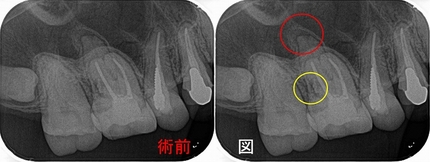

レントゲン

2026 EEdental YOA (1).jpg

外枠は外さず真ん中からくり抜くように治療したようです。

歯髄切断がしてありました。

2026 EEdental YOA (4).jpg

2026 EEdental YOA (3).jpg